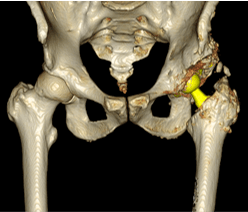

人工股関節手術後の経過

RAO後の人工股関節手術(THA)は手術難易度が格段に上がりますが、ALSアプローチでは術中X線透視装置を利用できるのでインプラントの正確な設置が可能となります。

難しい症例にも適応できる良い手術アプローチであると言えます。